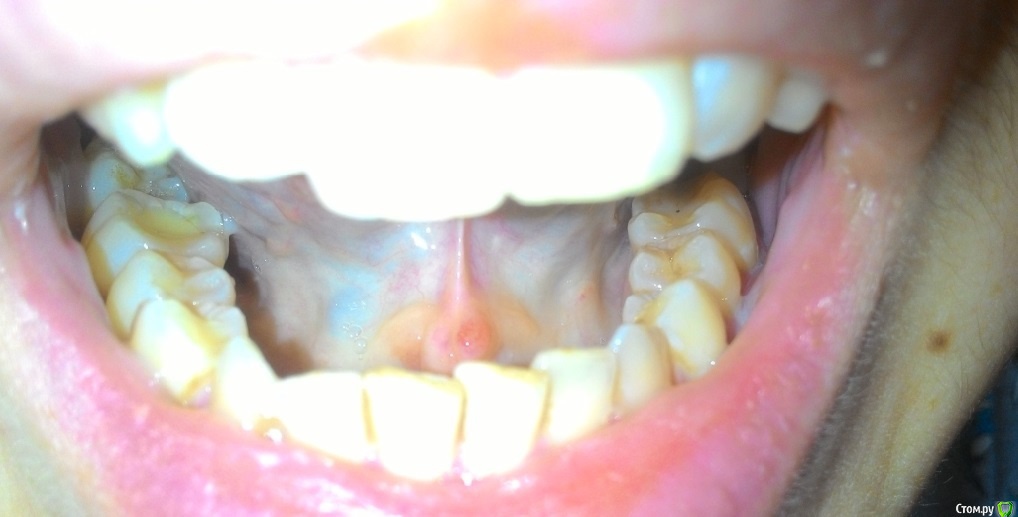

Пузырьки на уздечке под языком

На уздечке под языком у меня образовалось 2 пузырька.

28 декабря почувствовала, что как будто под языком что-то есть и оно мешается. Увидела эти пузырьки. Не болят.

29 декабря поехала снимать швы. Снимал другая доктор (мой был уже в отпуске), показала ей эти пузырьки, она сказала, что на вид пока не страшно, но что это - ей не понятно. Она показала меня еще другому доктору, та тоже сказала, что ничего страшного не видит, но толком не понимает, что это, порекомендовала наблюдать.

03 января - пузырьки сохраняются.